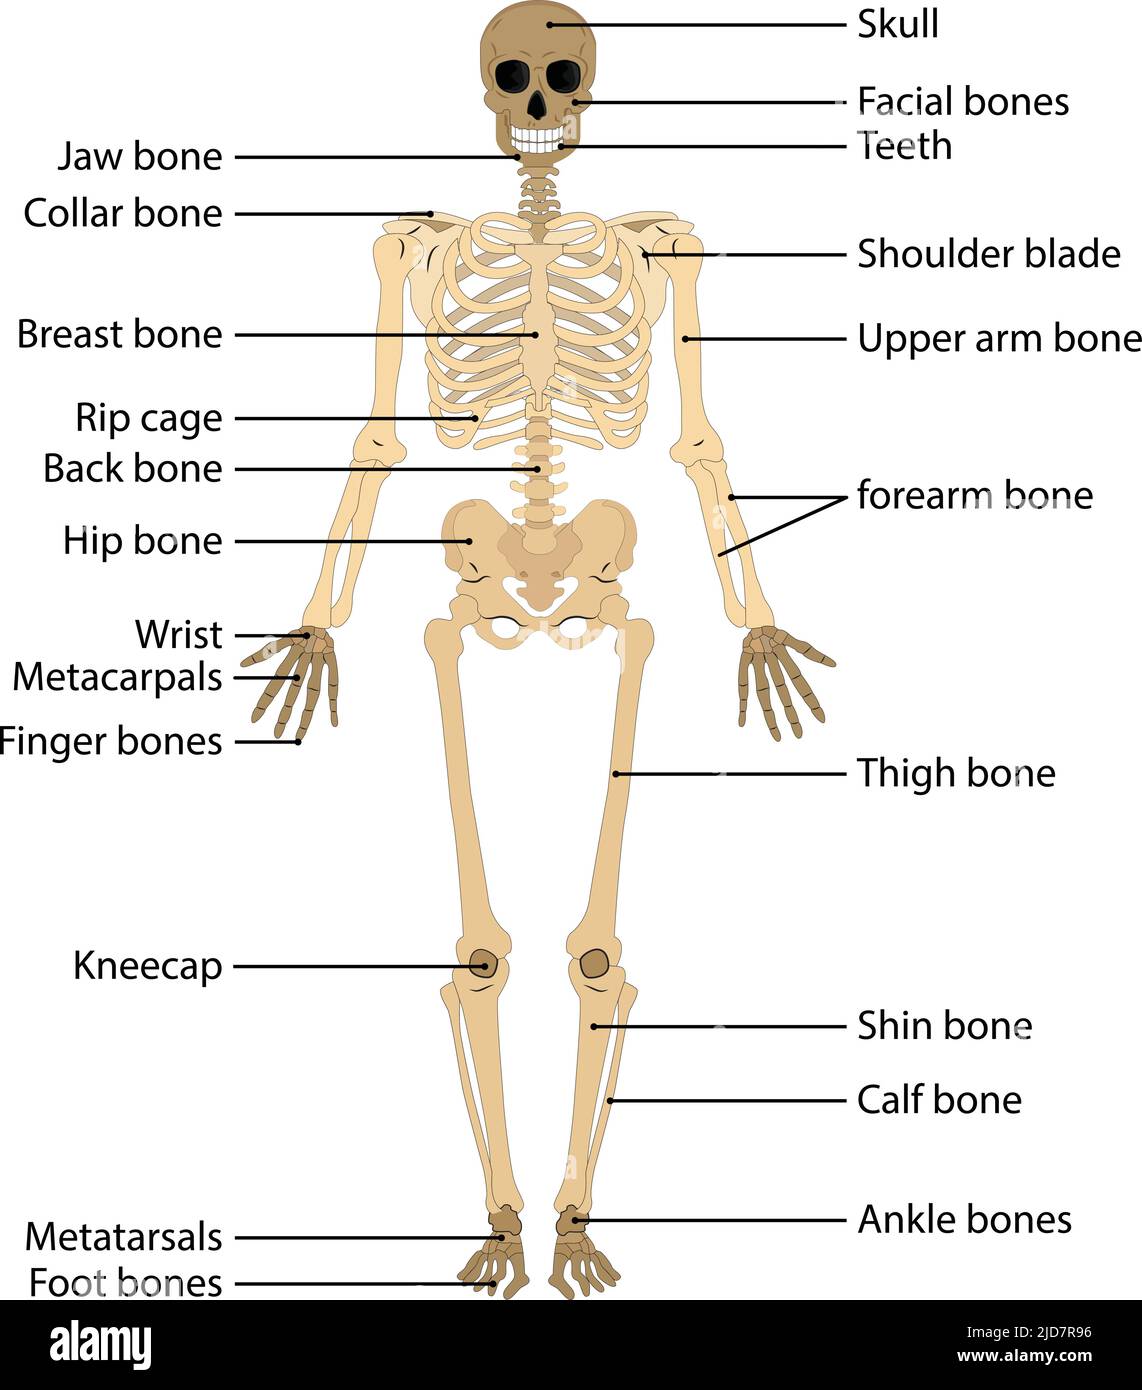

RF2JD7R96–anatomique, anatomie, dorsale, arrière-plan, biologie, noir, corps, os, cardiaque, circulation, dessin, élément, fémur, doigt, pied, avant, graphique, ha